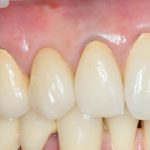

Рекомендации по установке имплантов. Для всех. Часть V.